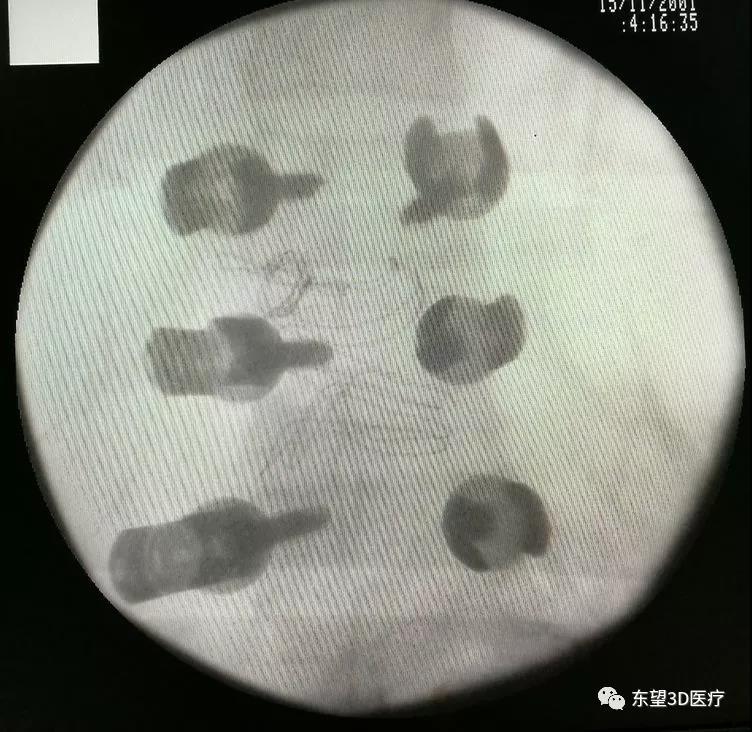

術中置釘、減壓見硬膜囊脊髓搏動良好

\

X線透視椎弓根釘位置準確